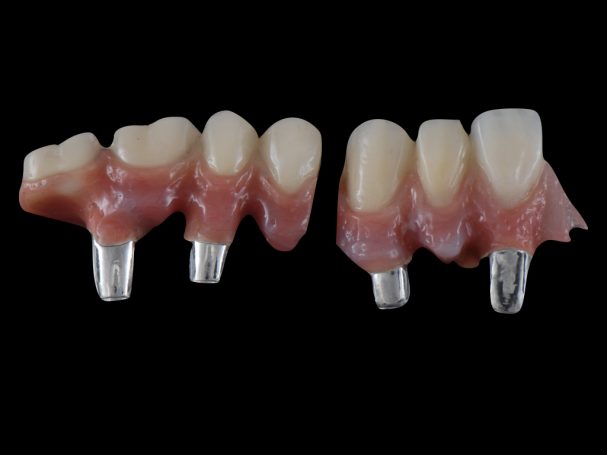

Implantatbrücke zur Wiederherstellung der Zahn- und Zahnfleischanteile mit verschraubten Brücken.